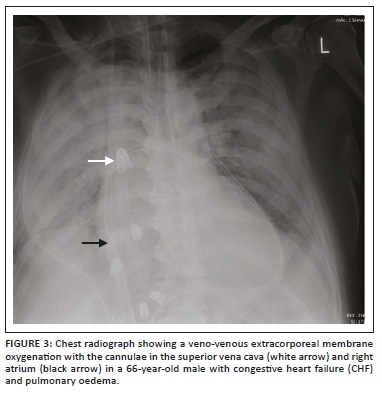

An intra-aortic balloon pump (IABP) is a polyethylene balloon that spans the entire length of the thoracic aorta, placed percutaneously via femoral artery access. The IABP comes in different lengths with IABP selection determined based on the patient's height. The IABP inflates during diastole leading to an increase in blood flow to the coronary arteries, great vessels and renal arteries. Immediately prior to systole, it deflates producing a vacuum effect leading to forward blood flow to the aorta and its branches. Although the IABP is predominately radiolucent on a CXR, it has radiopaque tips proximally and distally. On the CXR, the cephalad radiopaque tip should be 2 cm above the carina (Figure 1). An alternate landmark would be the aorto-pulmonary window. Placing the IABP too caudally may occlude the celiac, superior mesenteric or renal arteries, while placing it too high may occlude the brachiocephalic, subclavian or carotid arteries. Complications that can occur with IABP include vascular (e.g. limb ischaemia, renal insufficiency, mesenteric ischaemia and aortic dissection) and non-vascular (e.g. catheter-related [perforation, tear and incorrect positioning] infection and neurological sequelae).3,4,5

In VV ECMO, the femoral cannula tip should be at the junction of the inferior vena cava (IVC) and the right atrium (RA), and the internal jugular vein (IJV) cannula tip at the junction of the superior vena cava (SVC) and the RA. The VV ECMO dual lumen cannula (e.g. Avalon Elite) is inserted through the right IJV into the RA, with the tip in the IVC (Figures 2 and 3). Cannulation sites for VA ECMO cannulas depend on the device configuration, with femoral-femoral being the commonest3,6 (Figure 4). A change in the position of the cannula with reference to an adjacent bony landmark on subsequent radiographs should prompt the radiologist to check for ECMO malfunction. Misplacement of the ECMO cannula can lead to vessel obstruction or occlusion (e.g. SVC obstruction). Other complications that have been reported include gas emboli, thrombosis of veins or arteries, cerebral ischaemia or stroke and haemorrhage because of anticoagulation.6 A summary of the various ECMO configurations and their indications are elaborated in Table 1.